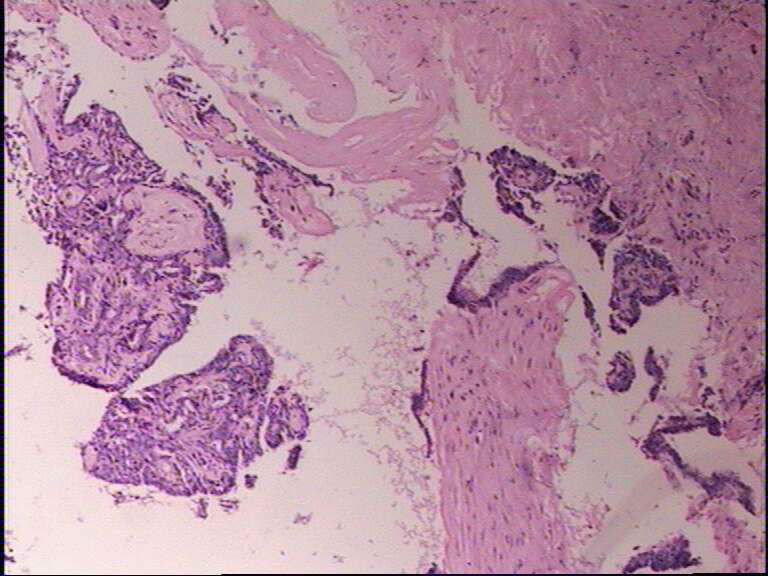

B3858乳腺肿物

女42岁,乳腺肿物一年

标签:乳腺导管内乳头状瘤

乳腺导管内乳头状瘤。

导管内乳头状瘤,可见肌上皮。